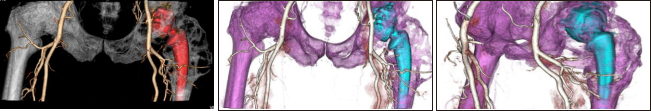

3、胸部應(yīng)用

病例一 女,30歲, 行巨乳癥術(shù)前CT檢查。

綠色血管是鎖骨下動(dòng)脈和內(nèi)乳動(dòng)脈。 紫色的是從內(nèi)乳動(dòng)脈上面發(fā)出來(lái)的胸廓內(nèi)動(dòng)脈, 主 要是滋養(yǎng)乳腺的內(nèi)上象限。 紅色血管是從腋動(dòng)脈發(fā)出的胸廓外動(dòng)脈, 滋養(yǎng)乳房的外下象限。

病例二 女,28歲, 胸部塑型術(shù)后復(fù)查。

運(yùn)用640層寬體探測(cè)器CT設(shè)備小焦點(diǎn)、高清模式的超低劑量智能追蹤法及動(dòng)態(tài)灌注掃描方式,通過(guò)了解鎖骨下動(dòng)脈、胸廓外動(dòng)脈、胸廓內(nèi)動(dòng)脈、腹淺動(dòng)脈以及遠(yuǎn)端分支,和所支配的從淺表到深部組織的供 血,方便對(duì)巨乳癥、乳腺癌皮瓣移植術(shù)后及胸部塑形等患者的精準(zhǔn)手術(shù),保證末梢循環(huán)和皮膚組織的供血,減少遠(yuǎn)端末梢組織的壞死以及并發(fā)癥。給臨床醫(yī)生進(jìn)行手術(shù)入路指導(dǎo)。